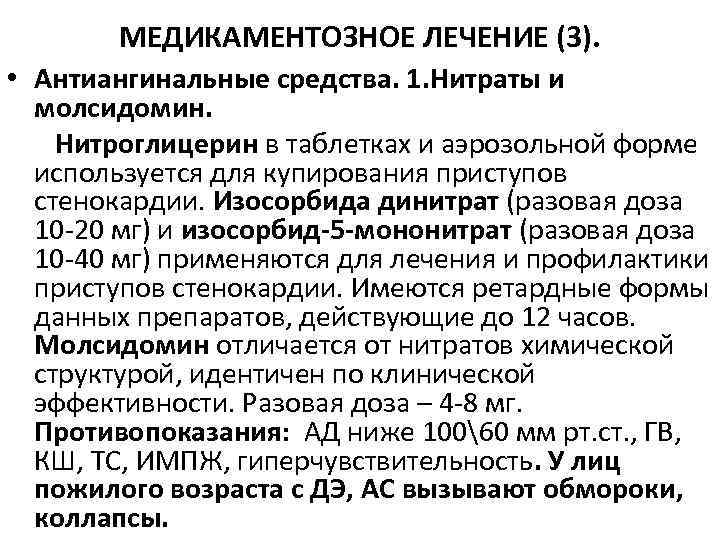

МЕДИКАМЕНТОЗНОЕ ЛЕЧЕНИЕ (3). • Антиангинальные средства. 1. Нитраты и молсидомин. Нитроглицерин в таблетках и аэрозольной форме используется для купирования приступов стенокардии. Изосорбида динитрат (разовая доза 10 -20 мг) и изосорбид-5 -мононитрат (разовая доза 10 -40 мг) применяются для лечения и профилактики приступов стенокардии. Имеются ретардные формы данных препаратов, действующие до 12 часов. Молсидомин отличается от нитратов химической структурой, идентичен по клинической эффективности. Разовая доза – 4 -8 мг. Противопоказания: АД ниже 10060 мм рт. ст. , ГВ, КШ, ТС, ИМПЖ, гиперчувствительность. У лиц пожилого возраста с ДЭ, АС вызывают обмороки, коллапсы.